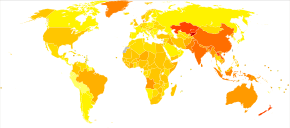

Globally, as of 2010, COPD affected approximately 329 million people (4.8% of the population).[10] The disease affects men and women almost equally, as there has been increased tobacco use among women in the developed world.[127] The increase in the developing world between 1970 and the 2000s is believed to be related to increasing rates of smoking in this region, an increasing population and an aging population due to fewer deaths from other causes such as infectious diseases.[5] Some developed countries have seen increased rates, some have remained stable and some have seen a decrease in COPD prevalence.[5] The global numbers are expected to continue increasing as risk factors remain common and the population continues to get older.[66]

Between 1990 and 2010 the number of deaths from COPD decreased slightly from 3.1 million to 2.9 million[128] and became the fourth leading cause of death.[5] In 2012 it became the third leading cause as the number of deaths rose again to 3.1 million.[129] In some countries, mortality has decreased in men but increased in women.[130] This is most likely due to rates of smoking in women and men becoming more similar.[15] COPD is more common in older people;[1] it affects 34–200 out of 1000 people older than 65 years, depending on the population under review.[1][62]

In England, an estimated 0.84 million people (of 50 million) have a diagnosis of COPD; this translates into approximately one person in 59 receiving a diagnosis of COPD at some point in their lives. In the most socioeconomically deprived parts of the country, one in 32 people were diagnosed with COPD, compared with one in 98 in the most affluent areas.[131] In the United States approximately 6.3% of the adult population, totaling approximately 15 million people, have been diagnosed with COPD.[132] 25 million people may have COPD if currently undiagnosed cases are included.[133] In 2011, there were approximately 730,000 hospitalizations in the United States for COPD.[134] In the United State, COPD, is estimated to be the third leading cause of death in 2011.[135]